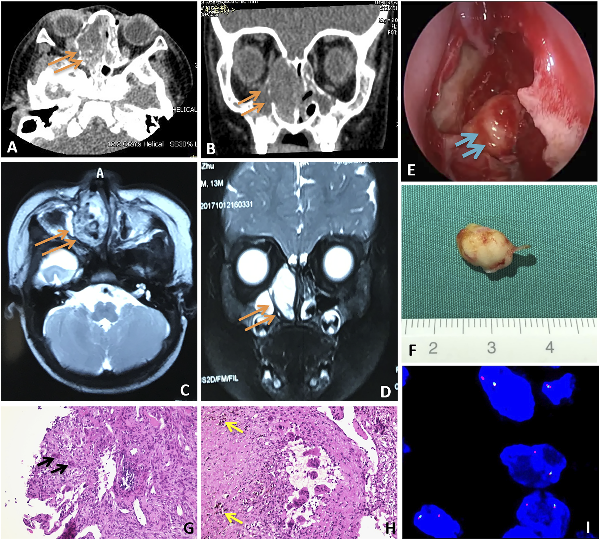

The patient was a one-year-old boy who had a right nasal obstruction for a whole month. The obstruction was progressive and obvious at night, and it was accompanied by intermittent nasal bleeding. A nasal examination revealed a firm red mass in the right nasal cavity. The tumor looked smooth and it was not separated from the surrounding mucous membrane tissue; it extended to the inferior conchae. There was no globe displacement or tooth loosening in the paranasal sinus area. In addition, there was no obvious abnormality in the results of the ophthalmic examination. The contrast-enhanced computed tomography (CECT) imaging of the orbits and paranasal sinuses showed complete opacification of the right ethmoid sinuses and nasal cavity (3.7 × 1.8 × 2.8 cm). However, the whole tumor had uneven enhancement and the boundary of the tumor was not clear. The mass compressed the maxillary sinus and the medial wall of the orbit. Erosion of the sinuses was observed (Figure 1 A.B). A magnetic resonance imaging (MRI) scan with gadolinium of the orbits and sinuses confirmed the unilateral pattern of sinus opacification within the right nasal cavity and ethmoid sinus. The lesion demonstrated multiple fluid–fluid levels and peripheral enhancement, considering the solid changes of the cyst with bleeding (Figure 1 C.D). The laboratory data (including a hematuria routine, serum calcium, serum alkaline phosphatase, and prothrombin time) were all normal.

Figure 1

CT Images of the ABC patient: The yellow arrow indicates the complete opacification of the right ethmoid sinuses and nasal cavity. The boundary of the tumor was not clear and had uneven enhancement. The mass compressed the maxillary sinus and the medial wall of the orbit. C.D: MRI Images of the ABC patient: The yellow arrow indicates a unilateral pattern of sinus opacification within the right nasal cavity and ethmoid sinus. The lesion demonstrated multiple fluid–fluid levels and peripheral enhancement, considering cyst solid change with hemorrhage. E.F: A yellow-white elliptical osteoma with a size of about 5 mm in diameter was seen at the patient’s middle nasal nail base plate. G.H: HE (hematoxylin and eosin) staining of the ABC patient’s pathological specimen. (G) The black arrow indicates multinucleated giant cells. ×200. (H) The yellow arrow indicates hemosiderin laden macrophages. ×200. I: The schematic diagram of FISH (fluorescence in situ hybridization) detection in children with ABC. It is suggested that USP6 breaks and translocates in tumor cells and is accompanied by loss of the green signal.

The patient underwent a nasal endoscopic tumor resection. During the operation, the lesion originated at the middle nasal meatus and contained several cystic areas filled with old blood secretion. A yellow-white elliptical osteoma (Figure 1 E.F) with a size of about 5 mm in diameter was seen at the middle nasal nail base plate. The mass was completely resected along the edge, and the right orbital wall disappeared. The orbital fascia was exposed and appeared intact, and the involved middle turbinate was resected. The patient had an uneventful recovery and was discharged on postoperative day 7.

The histopathological examination revealed a large number of incomplete lumens, as well as vascular extension which were filled with blood. In some areas, trabeculae of the reactive osteoid were present, as well as some hemosiderin laden macrophages and scattered multinucleated giant cells. The features were consistent with an ABC. An osteoma could be seen in the tissue, which was composed of spindle cells, polynuclear giant cells, and bone tissue. Osteoblasts were also seen around the bone (Figure 1 G.H).

It is known that aneurysmal bone cysts can be divided into primary and secondary types because of their different pathogeneses, but the child had no history of nasal trauma or bone tumors. Therefore, when a USP6 gene two-color separation probe for fluorescence was used, fluorescence in situ hybridization and the splitting apart of a green-orange probe signal indicated USP6 rearrangement. We found that 52% of spindle cells and multinucleated giant cells showed separate orange signals, 13% showed isolated red and green signals, 4% showed separate green signals, and 31% of negative cells (Figure 1 (i)). The results suggest that the child has USP6 rearrangement, which is a characteristic of primary ABC.